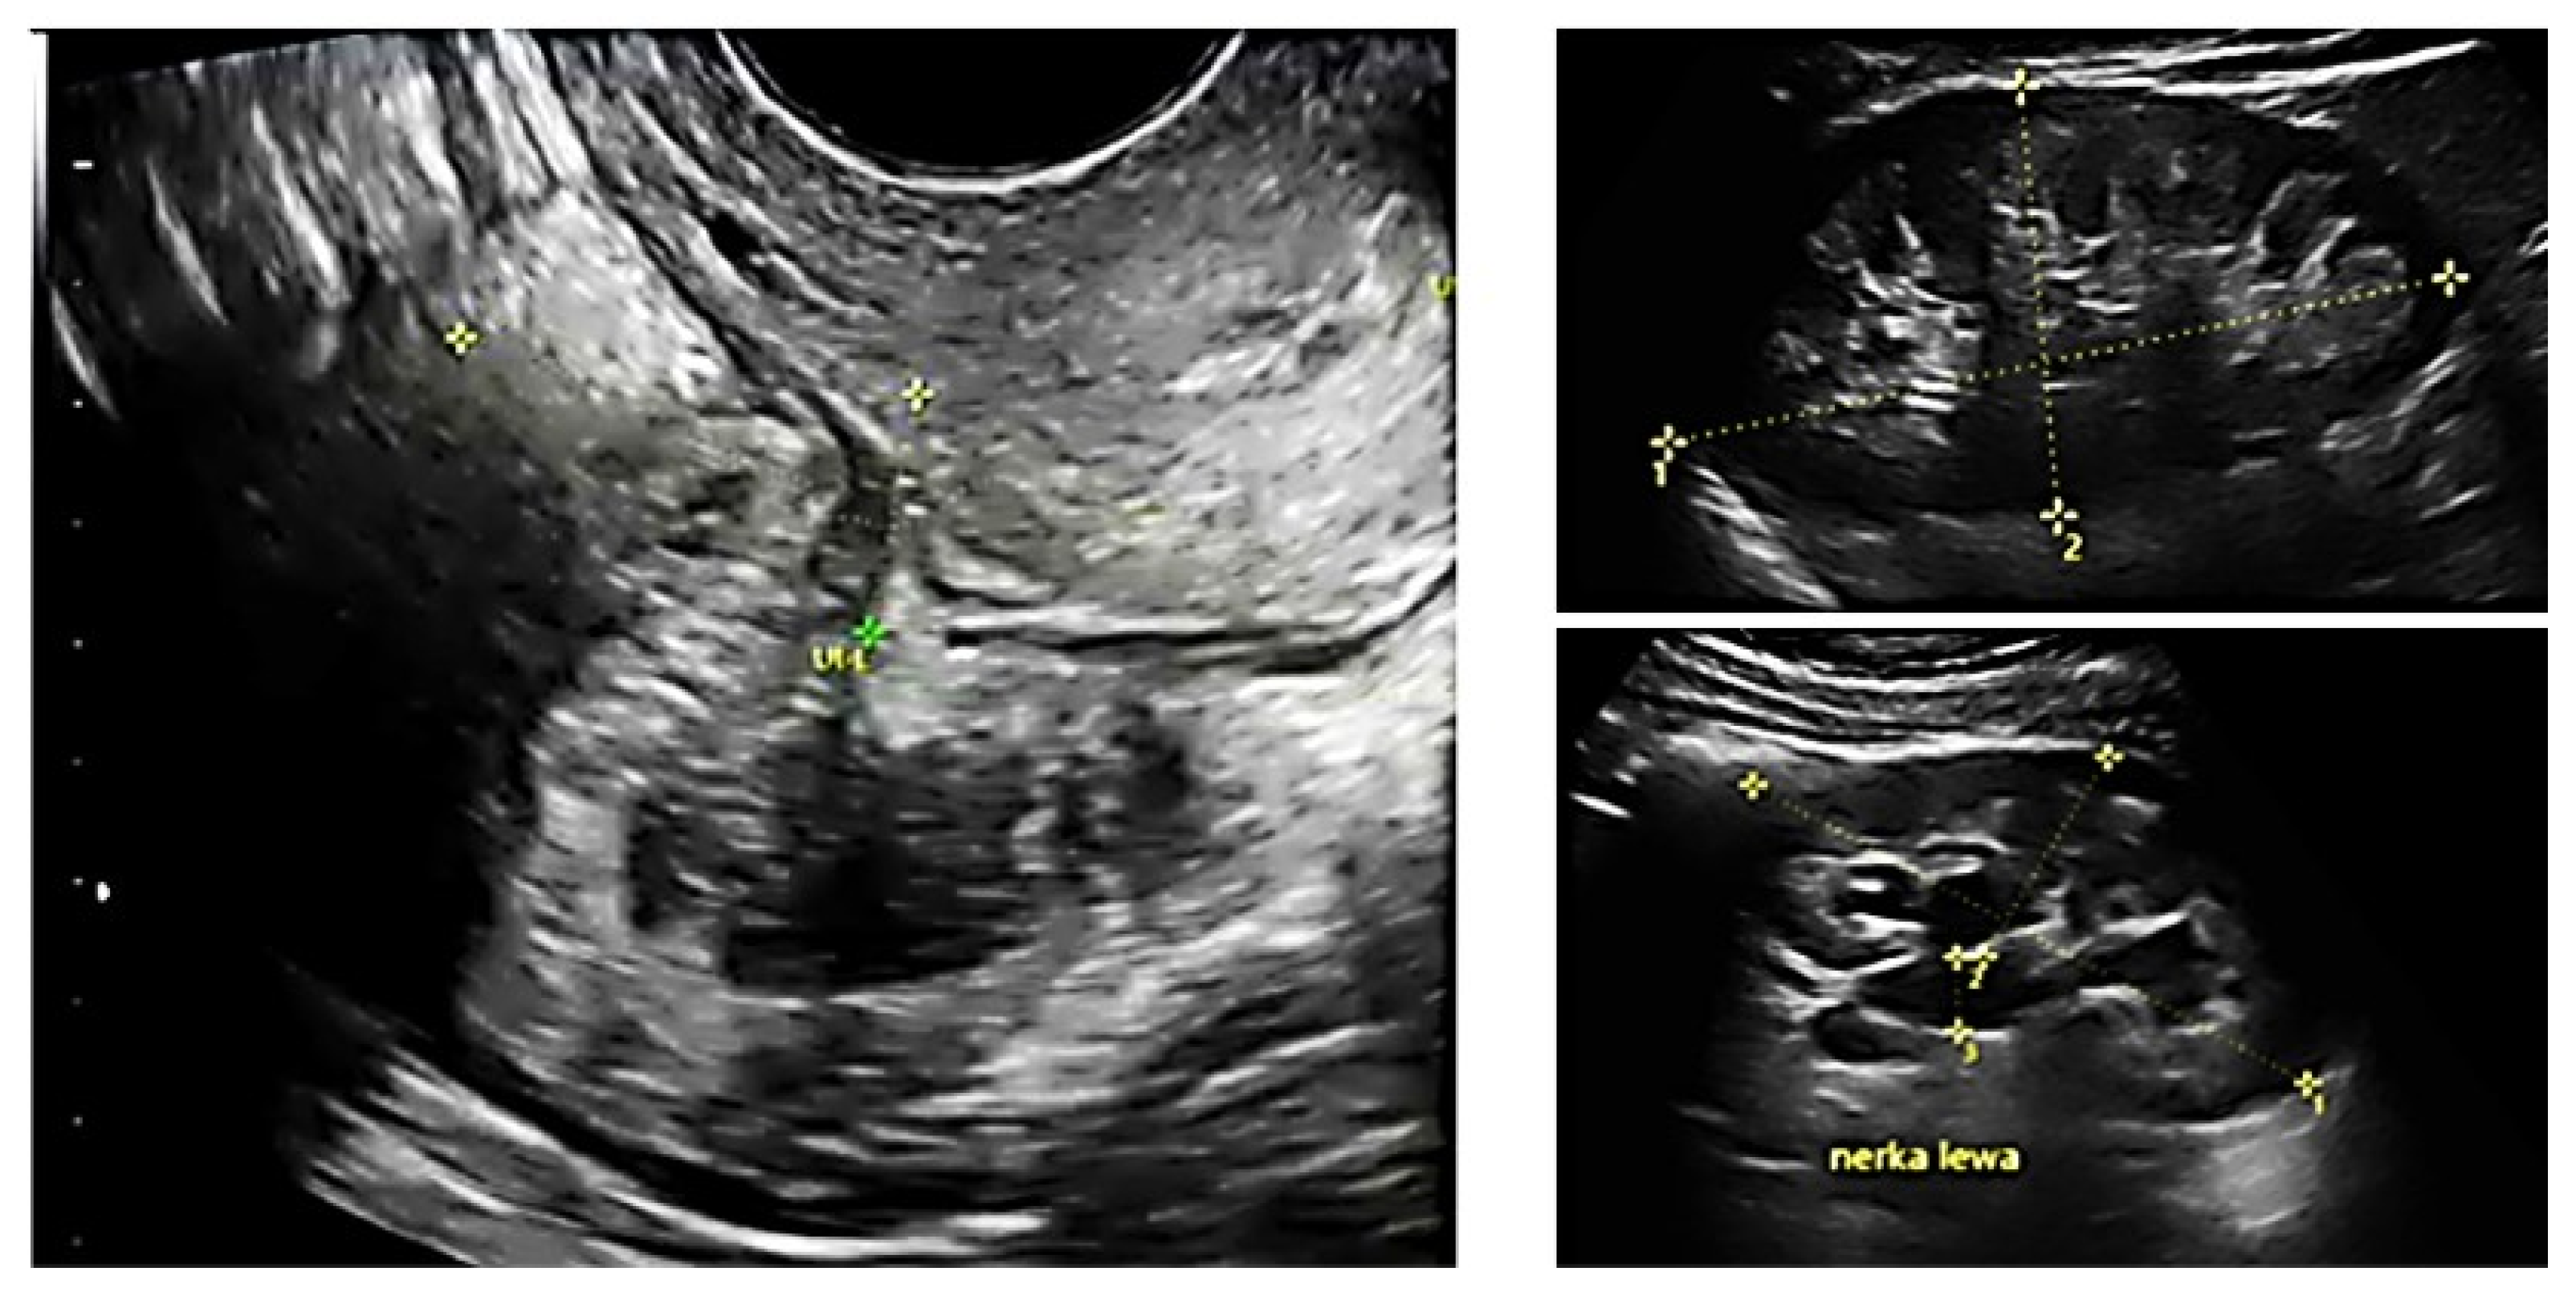

2.2. Ultrasound Examination

4.4. Ureters’ Assessment (Fu)

4.5. Why Would a Surgeon Use a Score?